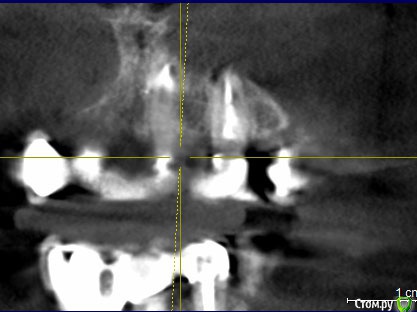

ira. k.. 78 Опубликовано 12 мая, 2020 Автор Поделиться Опубликовано 12 мая, 2020 Здравствуйте, вот такой ещё есть, больше срезов нет Ссылка на комментарий

It'sGeorgy Опубликовано 12 мая, 2020 Поделиться Опубликовано 12 мая, 2020 (изменено) ну если прямо сильно нажимаю на него то ощющение небольшой боли вроде есть, а так кушать не больно им, а что скажите по кт, я в срезах не понимаюНа КТ, действительно, есть очаг разрежения костной ткани вокруг этого зуба. При этом, сказать, что каналы запломбированы плохо - тоже нельзя. Я не терапевт, но со своей точки зрения вижу ситуацию так, что у зуба, на самой вершине, есть достаточно выраженный изгиб, что создало огромную трудность для доктора, который зуб лечил. Этот изгиб, к сожалению, запломбировать ко конца не получилось, что привело к развитию хронического воспаления.Повторюсь, я подобным лечением не занимаюсь и мое мнение может быть ошибочным. Поэтому, предлагаю подождать, пока вам ответит кто-то из здешних терапевтов. это не может быть от зуба?Такие ситуации могут быть от зуба, но тогда боль острая и постоянная. Плюс, тогда пациент сам может определить, что его беспокоит конкретный зуб. В вашем случае, как я понимаю, такого нет. Да и судя по снимку, остальные верхние зубы слева в порядке. делала кт 3 раза за годЕсли есть возможность, выкладывайте их тоже. Потому, что на снимке, который вы выложили очень много фоновых шумов, которые создают металлические конструкции во рту(мостовидные протезы). Возможно, по снимкам до изготовления постоянных конструкций будет видно и понятно лучше. Изменено 12 мая, 2020 пользователем It'sGeorgy Ссылка на комментарий

It'sGeorgy Опубликовано 13 мая, 2020 Поделиться Опубликовано 13 мая, 2020 (изменено) Скажите а штифт не помешает для ретроградного пломбирования, или его надо как то убирать? Штифт ставится не на всю длину канала, поэтому вряд ли он помешает. Выделил его красным на прикрепленном снимке. я нашла кт за март 2019 года, сейчас дам вам ссылку, это до протезирования. Сохраните этот снимок куда-нибудь отдельно, чтобы не потерять его. Он четче и информативнее. Изменено 13 мая, 2020 пользователем It'sGeorgy Ссылка на комментарий